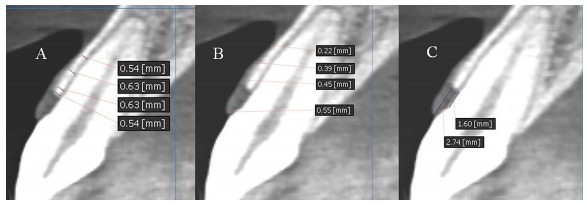

Assessment of gingival biotype and facial hardsoft tissue dimensions Releted TagsDr yaser safi gingival biotype hard tissue Maxillofacial Radiology Oral Radiology Radiography soft tissue Social Share